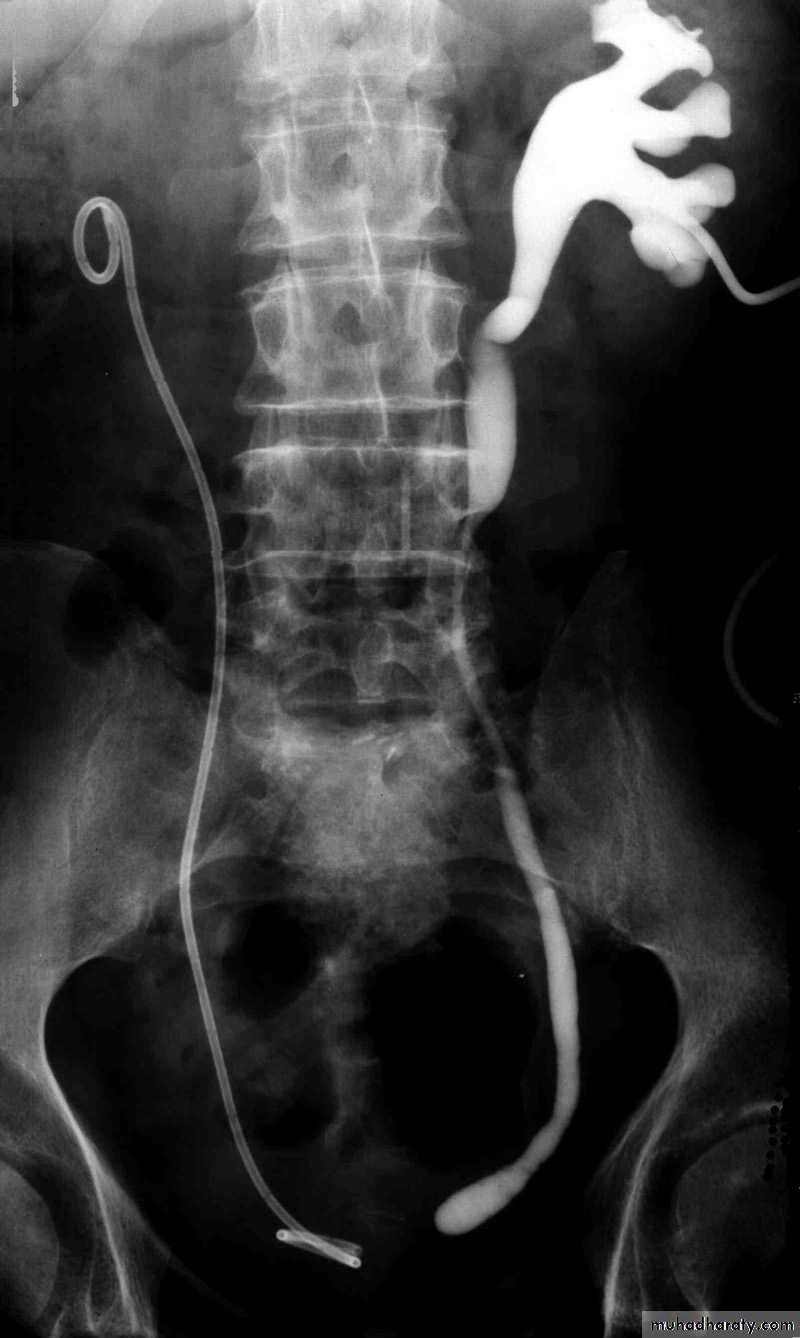

Postcaval (Retrocaval) ureter (Preureteral Vena Cava )

The right ureter pass behind the inferior vena cavaThis might causes obstruction

It is a vascular abnormality

Diagnosis: IVU

surgical correction involves ureteral division, with relocation and ureteroureteral or ureteropelvic reanastomosis, usually with excision or bypass of the retrocaval segment, which can be aperistaltic